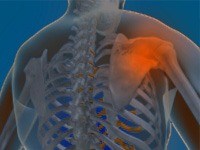

Rotator Cuff Tear

Rotator cuff is the group of tendons in the shoulder joint providing support and enabling wider range of motion. Major injury to these tendons may result in tear of these tendons and the condition is called as rotator cuff tear. It is one of the most common causes of shoulder pain in middle aged adults and older individuals.

Shoulder Impingement

Shoulder impingement is the condition of inflammation of the tendons of the shoulder joint. It is one of the most common causes of pain in the adult shoulder. The shoulder is a 'ball-and-socket' joint. A ‘ball' at the top of the upper arm bone, humerus, fits neatly into a 'socket’, called the glenoid, which is part of the shoulder blade, scapula. Shoulder impingement is also called as swimmer’s shoulder, tennis shoulder, or rotator cuff tendinitis.